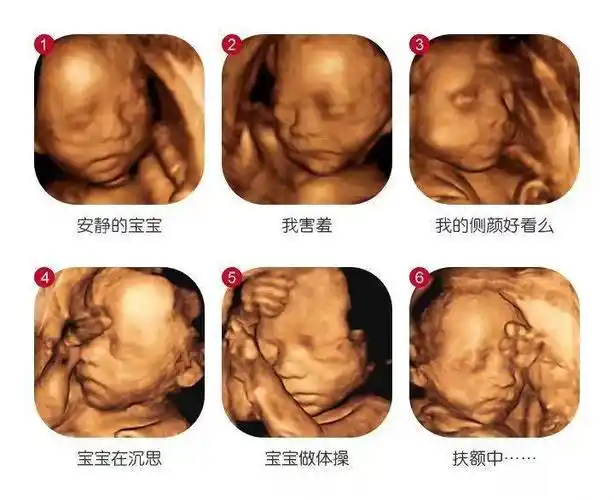

超声影像丨第一次与宝宝亲密会面留住爱最初的感动戳进来文末有福利